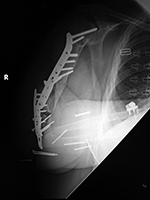

| 36 year-old man with bullet wound in 2003 complicated by femur fracture infected non-union treated by multiple attempts with external fixation and open reduction and internal fixation (ORIF). Radiography 12 years later shows chronic fracture hypertrophic nonunion, multiple shrapnel fragments, and breakage of a periarticular fixation plate. |